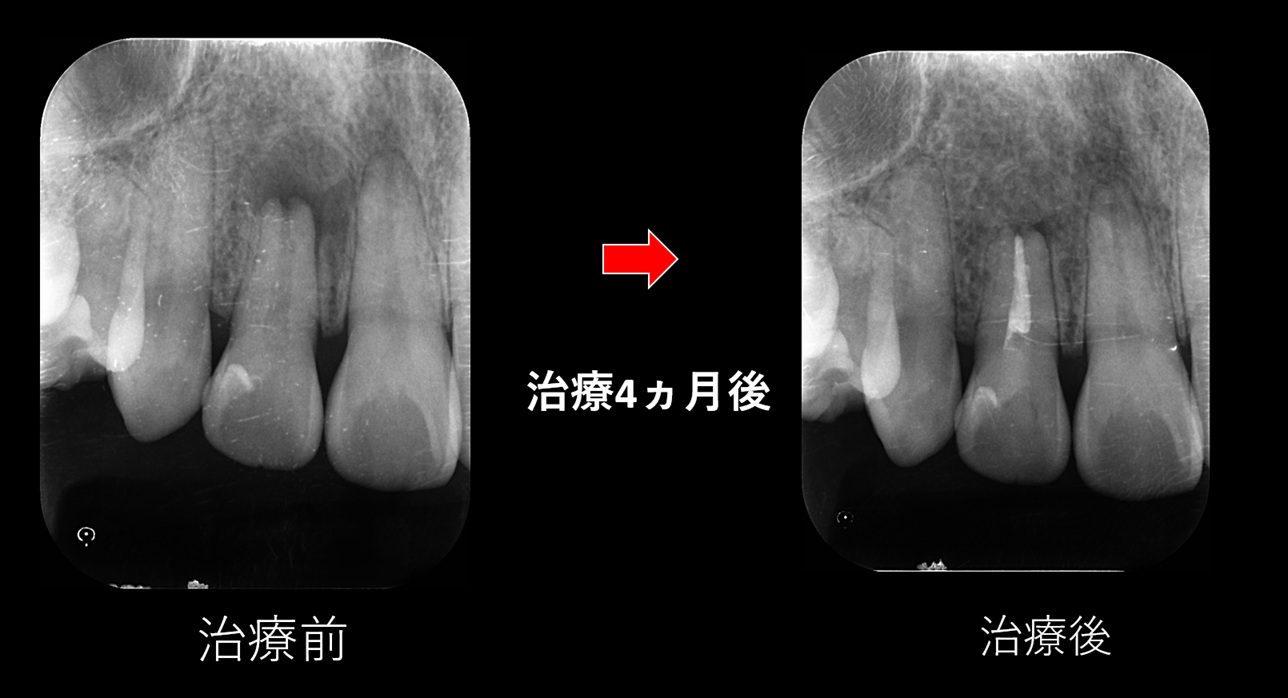

感染した部分を取り除き、炎症を抑える処置を行います。根管の内部は非常に細く、形状も複雑に入り組んでいるため、治療を担当する歯科医師に高度な技術と繊細な処置が求められる治療です。